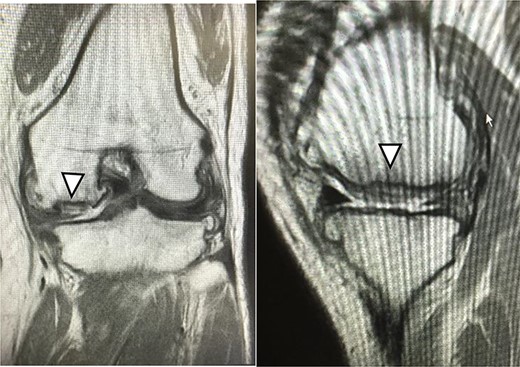

There were cartilage defects (arrowhead) in the medial femoral condyle and trochlea of the left knee (a, b).

A 42-year-old female (BMI, 27.4 kg/m2) presented with 2 years of left knee medial joint pain. Active range of motion (ROM) in the left knee was from 0 to 140 degrees with no extension lag. Preoperative Tegner scores, Lysholm scores and Knee Injury and Osteoarthritis Outcome (KOOS) scores are shown in Table 1. Preoperative radiographs of the left knee joint showed mild medial osteoarthritis (OA) of the knee and hip–knee–ankle (HKA) angle of 1.5-degree varus. 1.5-Tesla MRI was performed on unit (Toshiba, Kawasaki, Japan) was used with an extremity surface coil. Proton density images were obtained using the fast spin-echo technique. A modified magnetic resonance observation of cartilage repair tissue (MOCART) system was used for the quantitative evaluation of MRI findings of the cartilage injury [15–17]. MRI showed cartilage injury of the medial femoral condyle (MFC) and trochlea of the left knee (Fig. 1).

MRI showed cartilage injury of the medial femoral condyle (arrowhead).